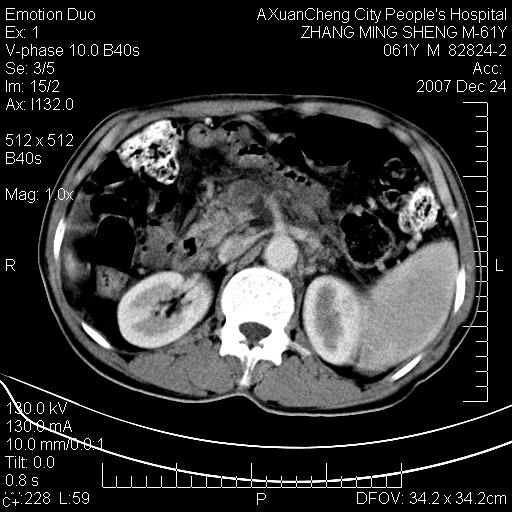

标题: CT11031:M61Y,胰腺占位

大家侃侃门静脉和胆管系统怎么回事,肝内转移?

1,肝硬化,脾大.

2,肝内多发结节状低密度占位,伴门脉及肠系膜上v栓子形成.考虑a;门脉及肠系膜上v血栓后肝改变.b;弥漫型肝癌伴门脉及肠系膜癌栓.

胰腺癌伴肝内转移;门脉、肠系膜上v癌栓形成。

考虑为:胰腺癌伴肝脏转移、腹膜后淋巴结转移,门静脉及肠系膜上静脉瘤栓形成。

胰体尾癌伴肝内转移,门静脉及肠系膜上静脉瘤栓形成.